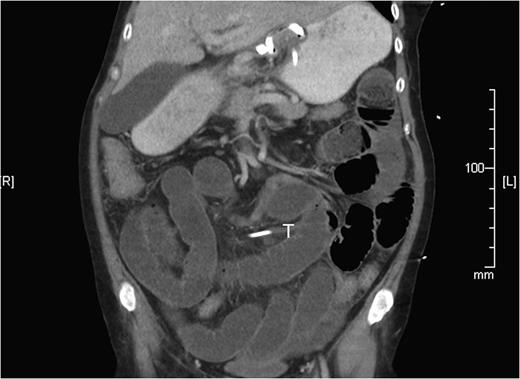

Two weeks later, she re-presented to the emergency department with a 24-hour history of severe central abdominal pain associated with vomiting and multiple episodes of loose stools. On examination, she was found to be hypotensive, tachycardic and peritonitic. The suspicion of an SBO was established by plain film radiograph appearances with multiple air fluid levels and distended bowel loops (Fig. 1). Computed tomography scan of the abdomen and pelvis showed the transitional zone to be in mid abdomen (Fig. 2). This was thought to be most likely secondary to adhesions. She proceeded on to have an emergency laparoscopy. Interestingly, the laparoscopy identified the transition point of the SBO to be an adhesion formed between the LAGB tube, the mid jejunum and the stomach forming a classic closed-loop obstruction (Fig. 3). The laparoscopic division of this adhesion was performed successfully. The rest of the small bowel was run along its entire length with no other transition point found. The adjustable gastric band was removed at the same time along with the associated port. Postoperatively, she had an uncomplicated recovery and was discharged on Day 4 post-admission without further sequelae.

Computed tomography reconstruction showing the SBO with transition zone in the mid ileum, later discovered to be caused by gastric band tubing (T).